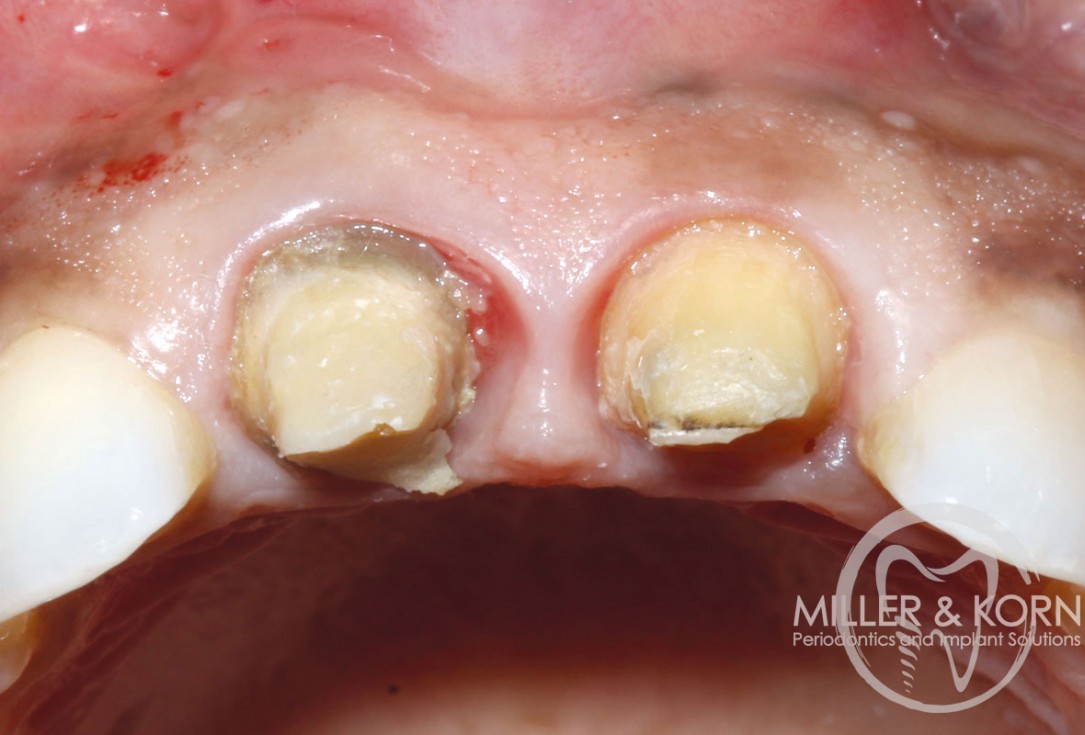

1/22 - 60-year-old female patient presented with a chronic infection on tooth #11. Since she has a high lip line matching the gingival margins of the adjacent central incisor and creating a root eminence is extremely important. For these reasons, the treatment of choice was an allograft bone ring enabling immediate placement of the dental implant with simultaneous regeneration of her ridge.Immediate implant placement and regeneration of ridge using an allograft bone ring and Jason® membrane - Drs. Miller and Korn

2/22 - She experienced trauma as a child and had fractured both tooth #8 and 9 which had been crown several times for esthetics.Immediate implant placement and regeneration of ridge using an allograft bone ring and Jason® membrane - Drs. Miller and Korn